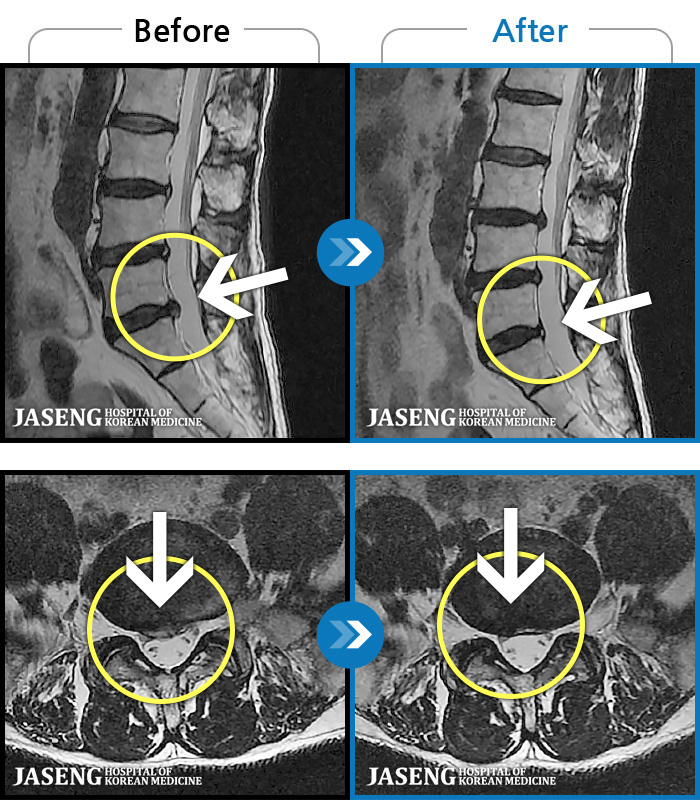

허리디스크

일산 · 김진수 원장

우측 골반 통증이 심하고 우측 하지로 당김과 저림이 지속되었습니다. 야간통이 심하여 야간 수면 제한이 되는 등 중등도 이상의 통증을 호소하는 상태였습니다.

촬영시기

2021.03.22 ~ 2025.09.30

2025.10.30